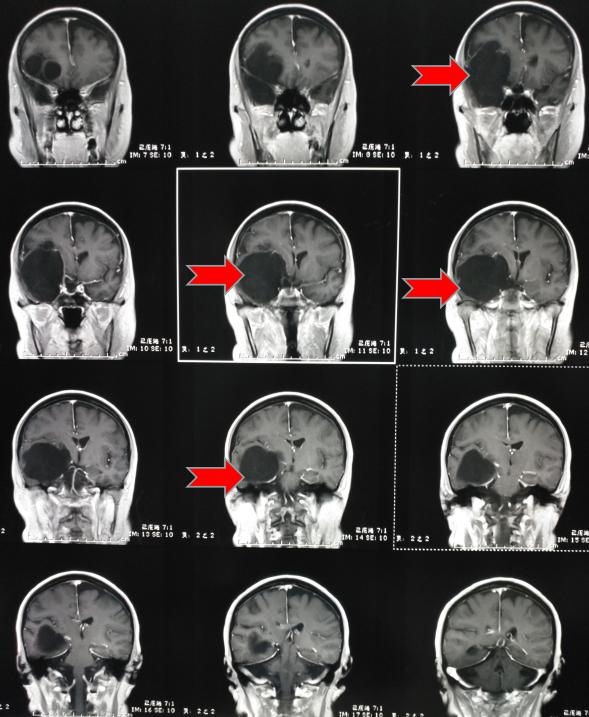

第二天趕緊到醫(yī)院看了一下,醫(yī)生說這是癲癇,隨后給她開了“丙戊酸鈉”長期口服,用藥后仍然每年有1-2次發(fā)作,大多是在晚上,有時(shí)即使沒有發(fā)生四肢抽搐,但有一種異樣的感覺。雖然這兩年很少發(fā)作了,但異樣感覺一直存在。今年她順利退休了,但教師的職業(yè)病——頸椎病卻讓他頸肩部以及上肢經(jīng)常麻木酸困,所以查了一下磁共振,確實(shí)存在頸椎病,但不需要手術(shù),只需保守治療即可。但意外的是發(fā)現(xiàn)了腦子里面長了個(gè)瘤子,大小約7厘米。

頭部磁共振提示腫瘤大小約7cm

一看片子,確認(rèn)是良性腫瘤,準(zhǔn)確點(diǎn)說應(yīng)該是一種叫做表皮樣囊腫的腫瘤,生長時(shí)間比較長,所以在早期很難發(fā)覺,經(jīng)常是在偶爾查頭部CT或者磁共振時(shí)發(fā)現(xiàn)。我給她說,這就是一直困擾她幾十年的病根所在,只要將它切除,她的癲癇和異樣感會(huì)逐漸消退,否則,隨著腫瘤增大,不僅會(huì)癲癇反復(fù)發(fā)作,而且會(huì)影響其他神經(jīng)功能??紤]再三,最終她還是選擇手術(shù)治療。